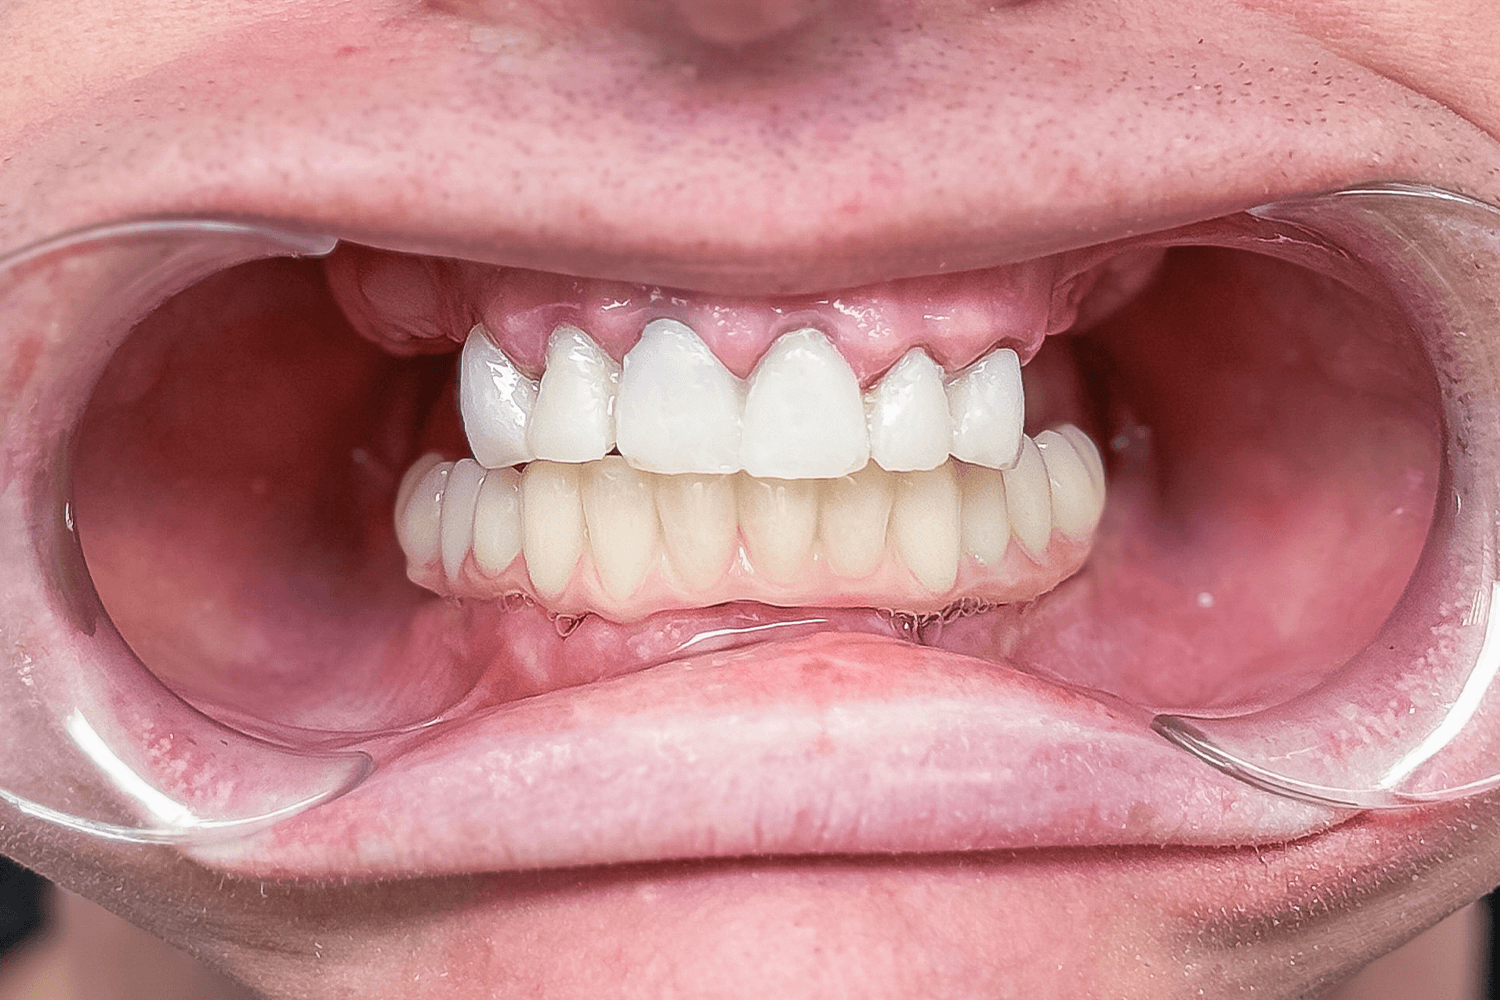

Изготовление и примерка mock-up модели

Через день пациенту перенесли mock-up модель в полость рта, подобрали цвет будущих зубов, еще раз согласовали форму и размер каждого зуба и отпустили с временными зубами отдыхать.